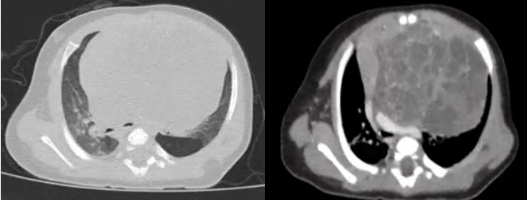

近日,一名僅2月齡、體重只有5.2kg的男嬰,因胸悶、呼吸困難來華西醫院小兒外科徐暢主任醫師處就診。經CT檢查發現,其縱隔內有一個巨大腫塊,最大直徑 7.4×6.0cm,像胸腔里長一個巨大的“石榴”,嚴重壓迫心臟、左主支氣管及肺動脈,不盡快摘除,隨時可能引發呼吸循環衰竭,危及生命。

患兒胸部CT影像